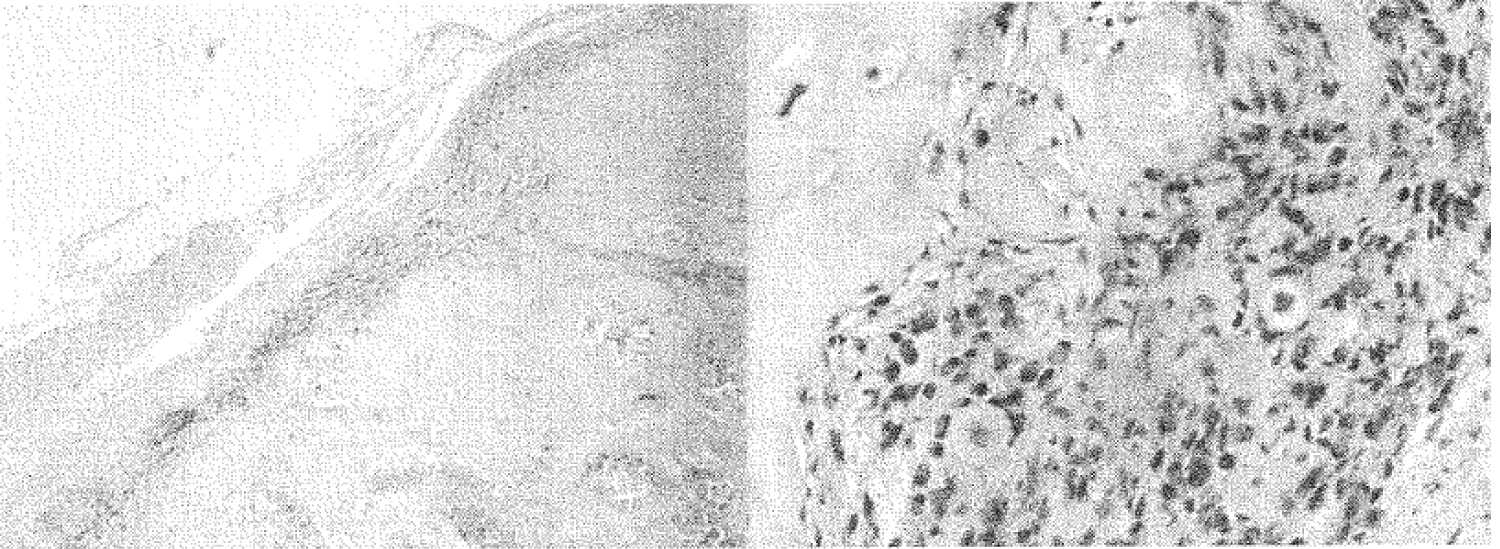

On histopathological examination, the diagnosis of SC was made. However, there were concerning features, particularly the presence of increased cellularity at the periphery of the nodules with spindling of chondrocytes and nuclear atypia. These histological features are not diagnostic however they raise suspicion for a chondrosarcoma developing in the SC. It was suggested that immunostaining be performed to clarify the presence of histiocytic differentiation in these atypical cells. CD163 and CD 68 were performed and showed that many of the atypical looking cells are histiocytic in nature. However, Ki67 proliferation was low and PHH3 immunostaining failed to identify definite mitotic activity in these regions. Therefore, there were no conclusive features of malignancy.

Patient was pain free post-surgery supporting a diagnosis of lateral impingement caused by the tumour mass. Bone tumour units in Royal Prince Alfred and New York Bone Tumour reviewed the histology as seen in Figure 2 and suggested complete excision of all SC deposits. Further resection was then performed and no malignant transformation identified (Figure 3).

Figure 2: Spindling and atypia of the cells seen at the perimeter of lobules. View Figure 2

An accurate diagnosis is made on the combined decision made from clinical findings, radiography (X-ray, MRI), and histopathology [12]. Histologically it is difficult to differentiate low-grade chondrosarcomas and SCs [13]. On histology, primary SC would be seen as lobules of hyaline cartilage that are frequently hypercellular with atypical histological features such multinucleation, nuclear crowding, nuclear enlargement and hyperchromasia with mild myxoid changes [14]. These atypical features could be interpreted as a low-grade chondrosarcoma when there is a high degree of cellularity and nuclear atypia. Another study discussed several histological features which favoured malignancy, and these include loss of clustering growth pattern typical of PSC, myoid change in the matrix, areas of necrosis, presence of mitotic figures and hypercellularity with spindling of the nuclei at the periphery [15], however might still not be accurate because they can be missed on resection [13].

The patient's histopathology report was concerning because of the high degree of spindling and atypia of the cells at the periphery of the lobules. These could be a feature of low-grade chondrosarcomas but Synovial Chondromatosis can develop such features as well mimicking a low-grade chondrosarcoma [13]. On immunostaining, Ki67 proliferation and mitotic activity was not found which would be other key features of malignancy. Another feature that was concerning for our patient was the size of the lesion. The high degree of spindling was a cause of worry when reviewed by the Bone Tumor Units and they suggested that the patient undergo a repeat surgery to completely remove any remaining deposits [19].